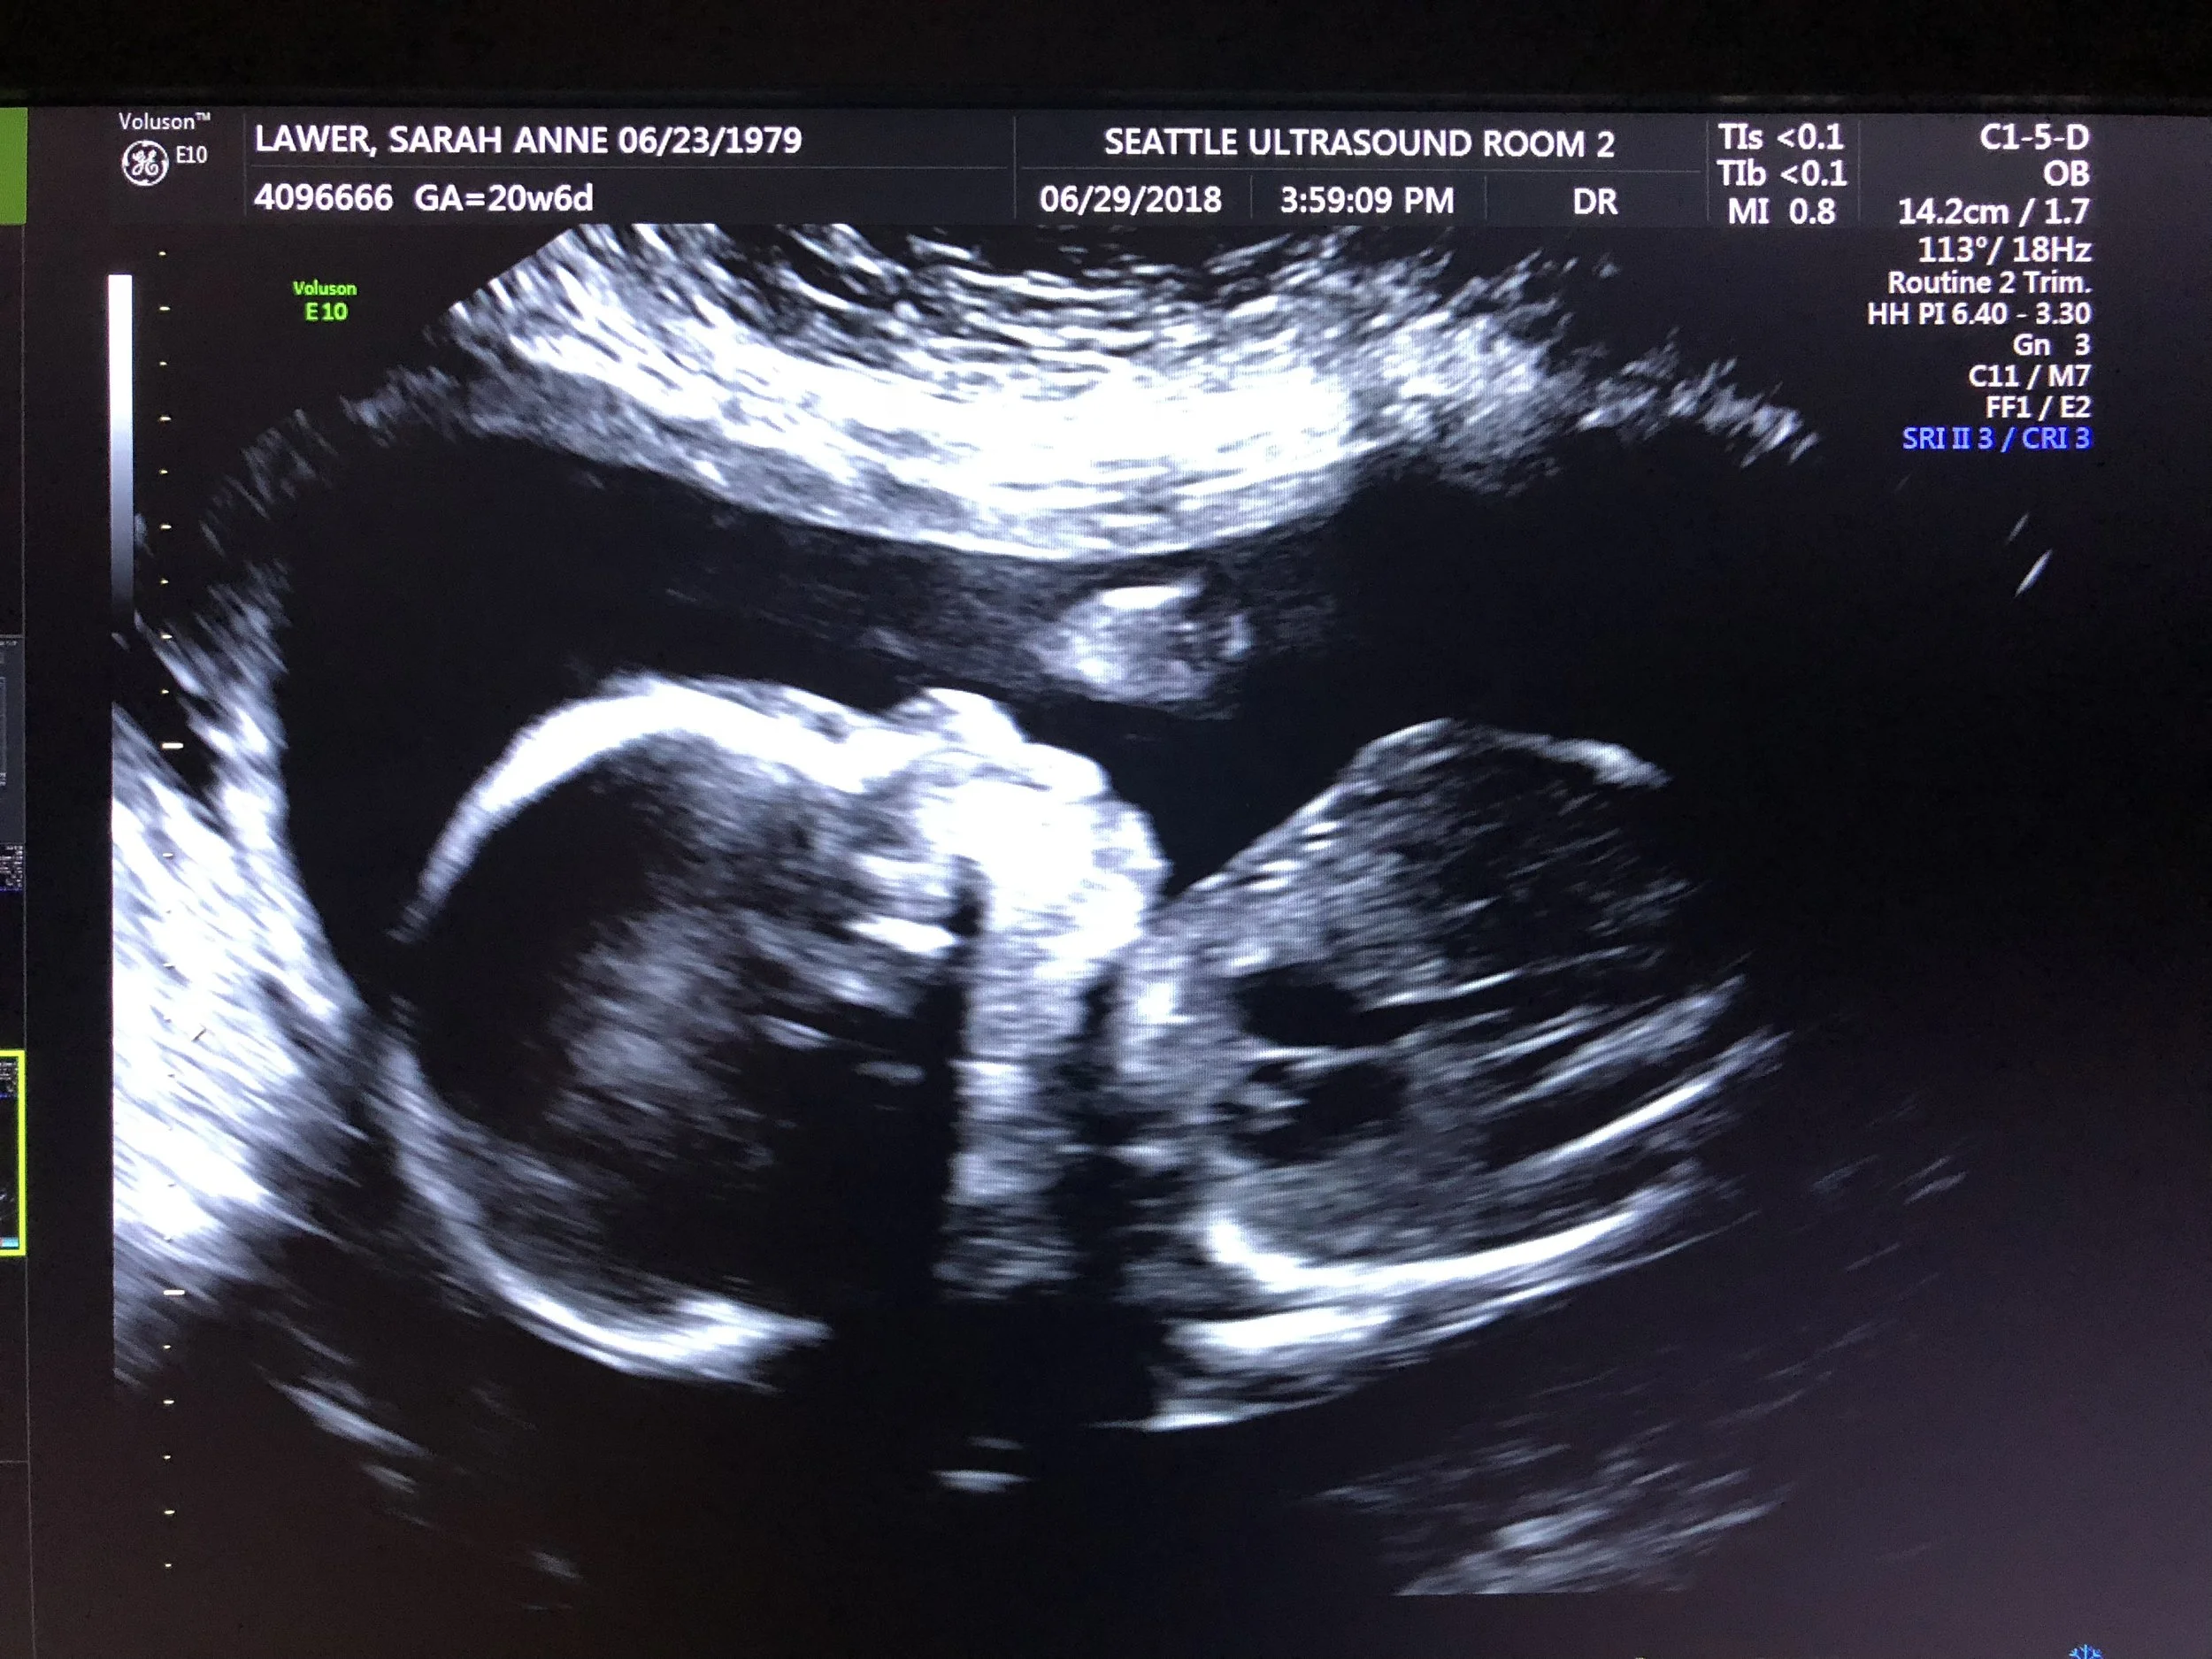

20 week ultrasound day! Officially half way there. The baby app says we have a banana, which the ultrasound measured to be 13oz...so, basically a can of Coke! Still, we are choosing not to know the gender. Until November 10th:)

IMAGE.JPG